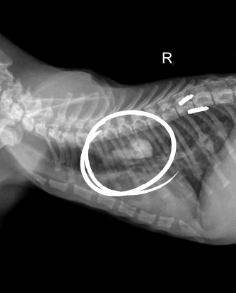

4살 된 강아지가 오른쪽 손목 부위를 과도하게 핥는 증상으로 2개월째 내원했습니다. 검사 결과, 두꺼워지고 탈모가 있으며 궤양이 있는 타원형 상처가 발견되었습니다. 임상 소견을 바탕으로 추측 진단은(acral lick dermatitis)입니다. 다음 중 옳지 않은 설명은 무엇인가요?